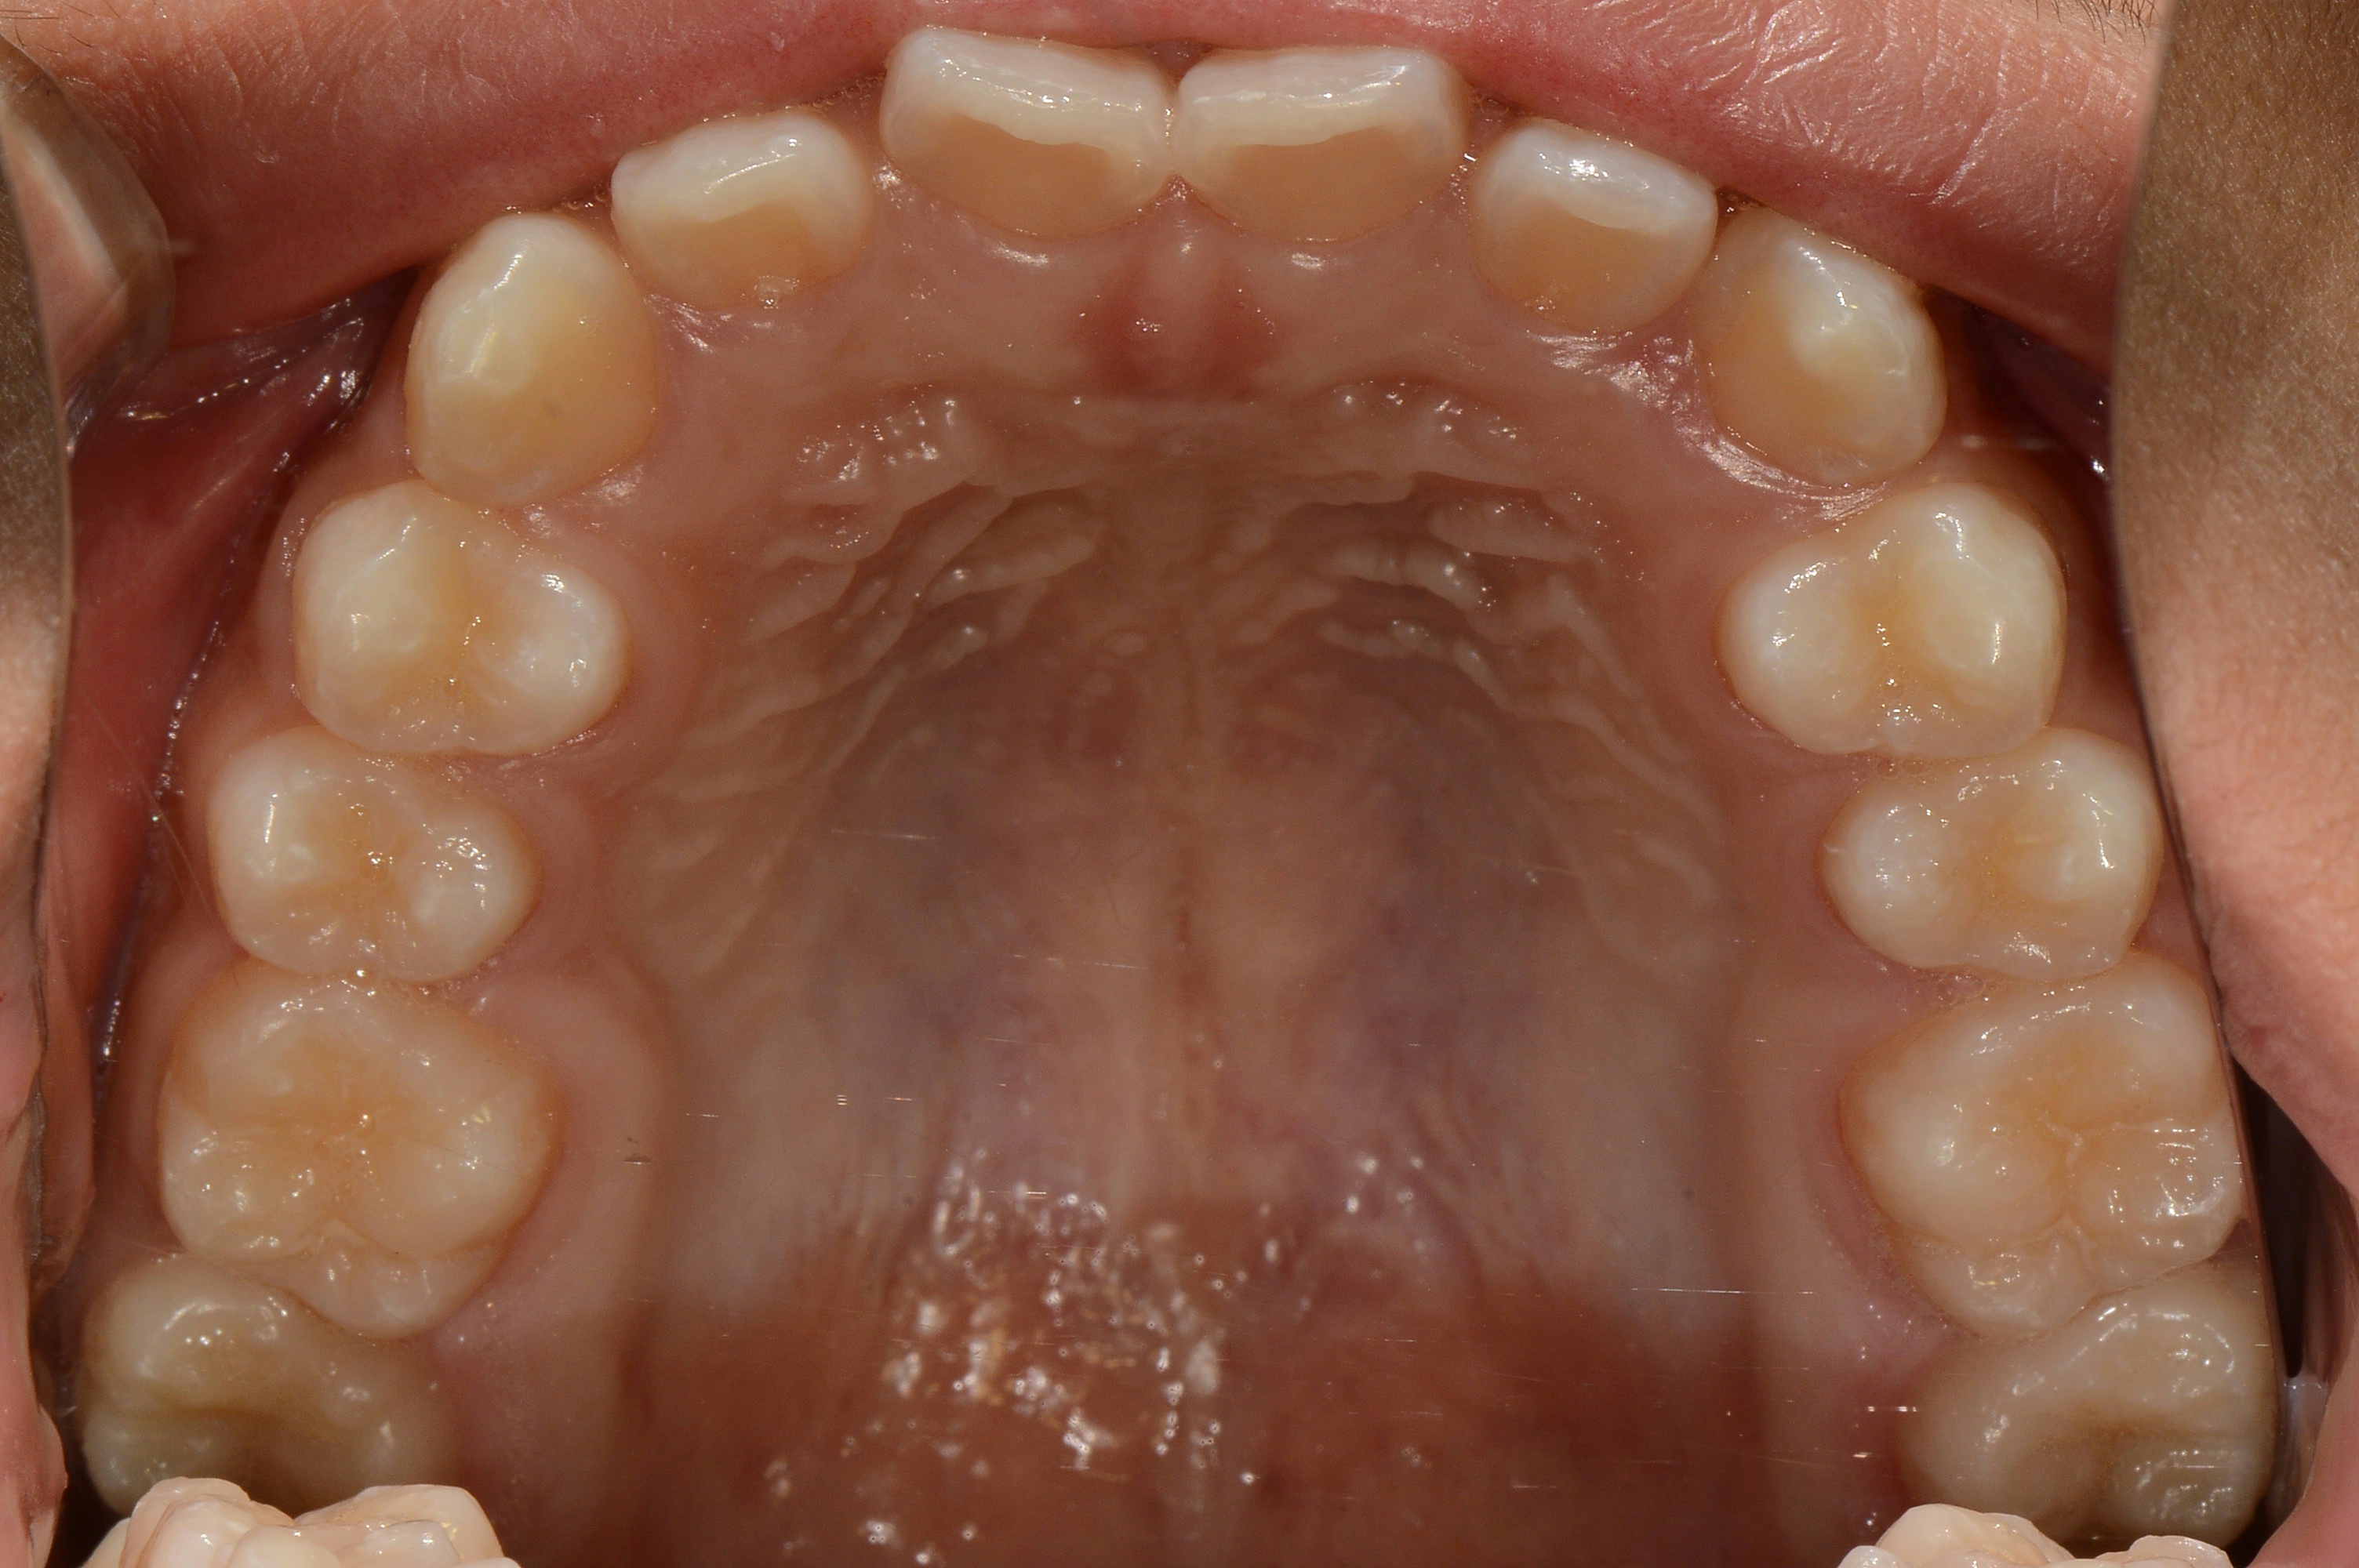

치료 전 사진입니다.